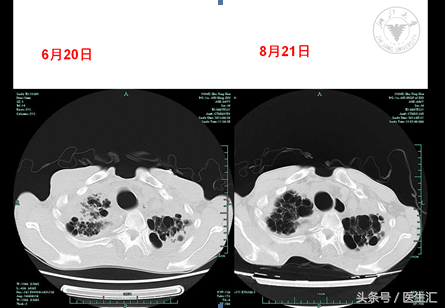

08-21增强扫描(一部位)):慢支、肺气肿伴两肺多发肺大泡;两肺间质性改变,左肺上叶病灶对比6月20日CT,部分病变有吸收好转。左上肺术后改变。两侧胸膜增厚粘连。